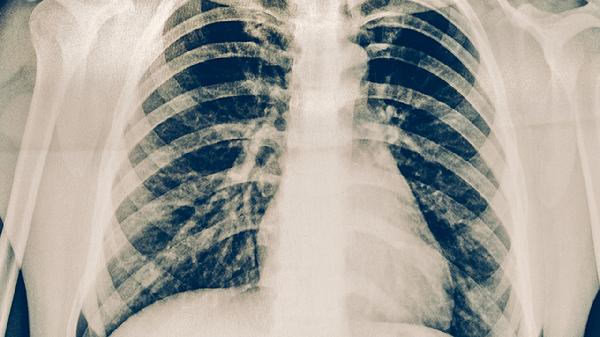

典型病變多位于肺上葉尖后段或下葉背段,呈現(xiàn)滲出、增生和壞死并存的多樣化病理改變。病灶中心可見干酪樣壞死,周圍環(huán)繞類上皮細(xì)胞和朗漢斯巨細(xì)胞,形成結(jié)核性肉芽腫。病變易發(fā)生液化空洞,成為重要傳染源。

痰涂片抗酸染色和結(jié)核菌培養(yǎng)是確診依據(jù),分子生物學(xué)檢測(cè)如GeneXpert可快速診斷。胸部X線可見上肺野斑片狀陰影伴空洞形成,CT能更清晰顯示病灶特征。結(jié)核菌素試驗(yàn)和γ-干擾素釋放試驗(yàn)有助于輔助診斷。